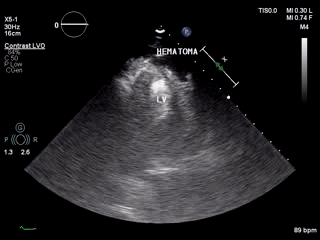

视频1:左室心尖可见团块状低回声,疑似血肿。

为进一步明确诊断,行床旁心脏超声造影,可见Contrast-LVO模式下,可见心包腔内可见由左室心尖缓慢飘出的点状造影剂声像。

视频4 :心尖外心包腔处可见一团块状低回声区,边界尚清,内部未见明显的造影剂回声。

视频5-6 :心脏超声造影提示:右室流出道与左室心尖间外壁血肿形成。中大量心包积液。

图5: 2017年8月30日复查经胸超声心动图提示:左室靠近心尖处血肿形成。少量心包积液。左室靠近心尖处外壁可见一低回声包块,大小约40mmx21mm,边界尚清。